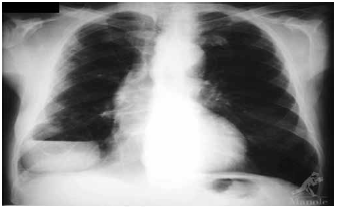

Paciente etilista, com dentes em mau estado de conservação, apresenta quadro de febre e tosse. O RX encontra-se a seguir. O tratamento mais indicado, nesse momento, é feito com

A

ampicilina.

B

amoxacilina.

C

levofloxacino.

D

piperacilina-tazobactam.

E

ceftriaxone.